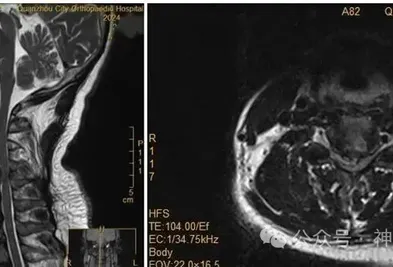

夜間翻身取手機(jī)突發(fā)癱瘓!醫(yī)生警示:這些頸椎癥狀需警惕 近日福建泉州一位50多歲的王女士遭遇了一場意外變故她在夜里翻身伸手拿手機(jī)時突然出現(xiàn)雙上肢癱瘓的情況連抬手的力氣都沒有了此前,王女士因手麻、酸痛到醫(yī)院就診,被診斷為頸椎間盤突出癥。主治醫(yī)師回憶:“會診時 6小時前